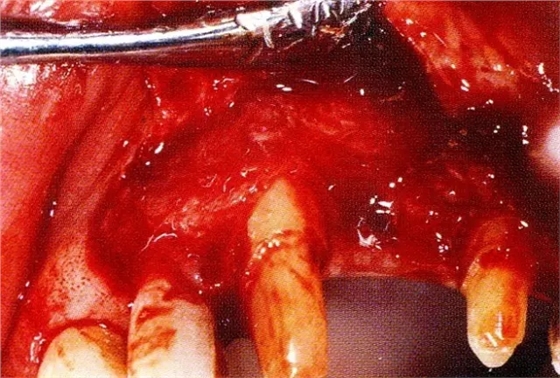

▲圖7-4術(shù)后1年2個(gè)月再翻開看的情況。與圖7-1的骨缺損狀態(tài)相比可知形成了臨床性骨再生。

▲圖7-5此狀態(tài)下,左下5的遠(yuǎn)中存在牙槽骨不平整,因此進(jìn)行了骨修整。同時(shí),將骨膜留存,進(jìn)行了齦瓣根尖側(cè)移動(dòng)術(shù),去除了牙周袋。